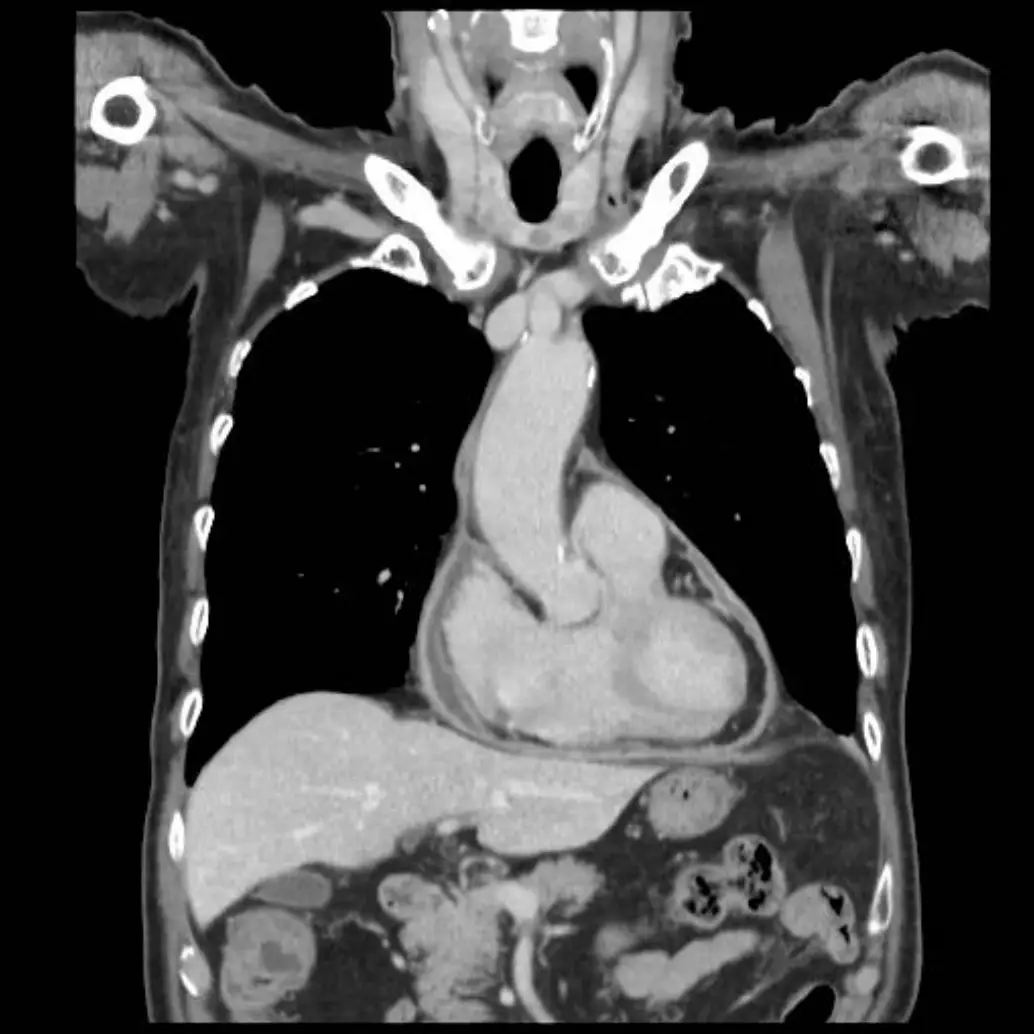

病人王先生現年88歲,有兩個月的雙腳浮腫及運動性呼吸困難,數度前往多家醫院求診,診療罔效。病人 有多年高血壓、高脂血、慢性腎臟病及前列腺肥大等過往病史。到診時意識清醒, T/P/R: 35.5 °C/99/18; BP: 106/83 mmHg; SpO₂: 92%。(ambient air); BH: 165 cm; BW: 66 kg; BMI: 24.2 kg/m² 理學檢查發現 顏面微腫,頸靜脈中度怒張,脈搏稍弱,並未有顯著Paradoxical pulse, 及Kussmaul sign,呼吸聲清 淨,心臟大小正常,心音略遠,P2稍強,Pericardial friction可疑,無肝、脾腫大,雙腳微腫。其心電 圖、胸部X光及其他影像檢查如圖:請問依照上列數個標的之理學檢查 (Targeted physical examination) 及實驗室所見,這位病人最可能的診斷是

心包積液及心臟壓塞(cardiac tamponade)的臨床表現、電圖特徵與多模態影像診斷。

影像分析:

- 胸部X光:心影擴大呈「水瓶狀」輪廓,心臟外形圓鈍平滑,肺野無明顯充血或水腫,符合大量心包積液造成的心影變化(en.wikipedia.org)